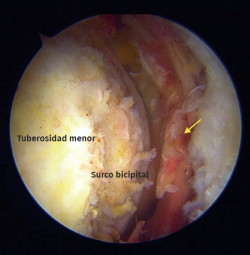

La misma técnica de reparación estandarizada fue utilizada en todos los pacientes por el mismo cirujano (M.L.), como se explica a continuación. La reparación artroscópica de la lesión se realiza en posición de silla de playa bajo anestesia general en combinación con un bloqueo regional interescalénico guiado por ecografía. Se utiliza un posicionador neumático para manejar la extremidad. Se realizó una exploración artroscópica inicial. En lo que respecta a los portales de trabajo, se desarrollaron un portal anterior inmediatamente lateral al coracoides a través del cual se coloca una cánula de 8 mm, así como un portal anterolateral de visualización no convencional(7) (Figura 2) y un portal lateral accesorio para el manejo de suturas (Figura 3). Utilizando un endoscopio de 30° a través del portal anterolateral, se realiza una bursectomía y un desbridamiento utilizando una rasuradora de hoja curva y radiofrecuencia alrededor de la tuberosidad menor y el surco bicipital. Los tejidos blandos se liberan con radiofrecuencia a nivel del intervalo rotador, en la cara anterior del tendón hacia el cuello anterior del glenoides y en la región posterolateral del coracoides hasta que se restablece la excursión del tendón(4). En este paso se identifican el nervio axilar y los nervios subescapular superior e inferior durante la disección para evitar lesiones inadvertidas.

Figura 2. Vista artroscópica desde el portal anterolateral en un hombro derecho en posición de silla de playa. Rotura crónica del tendón del bíceps. Flecha: espesor total y retracción del tendón subescapular.